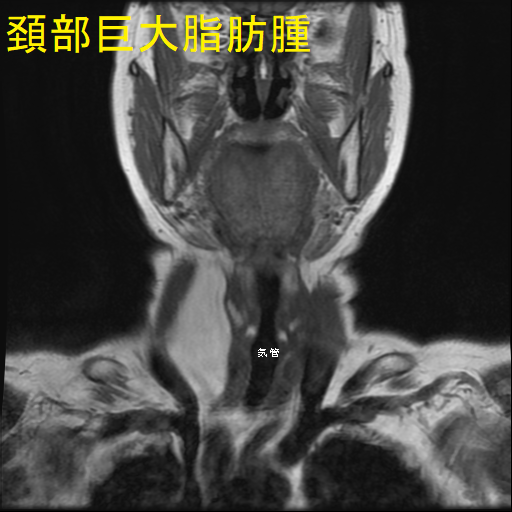

巨大頚部脂肪腫